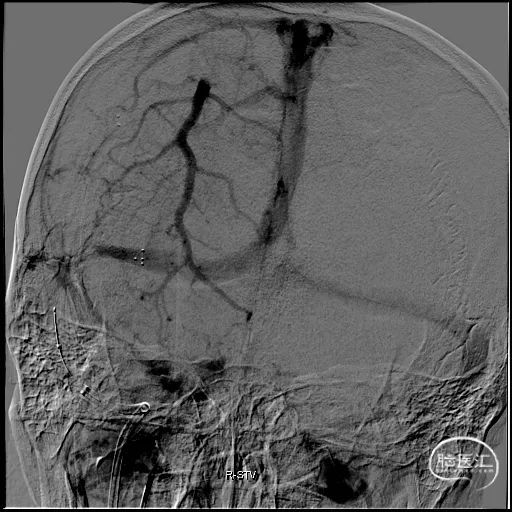

c) 大口径抽吸导管开通上矢状窦:

图注4:

4A 微导丝/微导管/ Penumbra ACE68 同轴技术向前推进至上矢状窦、引导ACE68进入上矢状窦远端

4B 侧位动态记录可以看到 ACE68良好的通过性

4C 微导管正位造影剂推注明确上矢状窦及窦汇区域也有大量栓子信号

4D 撤出微导丝及微导管, ACE68大口径抽吸窦汇区域,吸出大量血栓

4E 桡动脉造影提示上矢状窦仍有大量血栓,拟进一步推进ACE68 进行抽吸治疗

4F 微导丝微导管引导ACE68进入上矢状窦远端

4G-H 上矢状窦内ACE68反复抽吸后,造影可见上矢状窦恢复正常回流